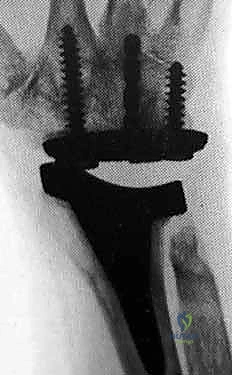

The evolution of modern implant design has capitalized on modularity, superior tribology, and improved anatomic geometries to provide enhanced longevity. A great debt of gratitude is owed to Dr. Jay Menon for popularizing stable distal screw fixation into the carpus, fundamentally altering the biomechanical paradigm by avoiding the destructive lever arm created by a long intramedullary stem inserted into the third metacarpal. Today, the three most popular wrist designs utilized in the United States are the Universal 2 (KMI/Integra), the Re-Motion (Small Bone Innovations [SBI]), and the Maestro (Biomet). The Universal 2 Total Wrist prosthesis, an improved version of Dr. Menon's original design, utilizes a flat carpal cut, screw fixation distally into both the second metacarpal and hamate, and a modular, distally based polyethylene cap that articulates with a proximal cobalt chrome radial component.

Following capitate reaming, the chosen carpal plate and stem are assembled and inserted into the capitate and seated onto the resected carpal surface. The carpal plate is anchored to the carpus with a radial screw that optimally does not penetrate the second metacarpal, and a second screw placed ulnarly into the hamate. This construct ensures stable distal fixation while avoiding the deleterious lever arm of a long metacarpal stem. Trial reductions are performed to assess stability, range of motion, and impingement. Once kinematics are confirmed, the definitive ultra-high-molecular-weight polyethylene (UHMWPE) body—which is direct compression molded onto a cobalt chrome alloy radial body—is impacted. The capsule and extensor retinaculum are meticulously repaired to prevent extensor tendon bowstringing and provide a robust soft tissue envelope over the implant.

Biomechanical studies have definitively validated the paradigm shift away from metacarpal intramedullary stems. Finite element analysis and cadaveric kinematic studies have shown that distal screw fixation into the carpus, combined with a broad carpal plate, more evenly distributes compressive loads across the midcarpal joint and vastly reduces the shear forces that lead to early osteolysis. Furthermore, comparative cohort studies have repeatedly demonstrated that patients who undergo TWA report higher satisfaction rates and better ability to perform personal hygiene tasks compared to matched cohorts undergoing total wrist arthrodesis.

Clinical & Radiographic Imaging Archive